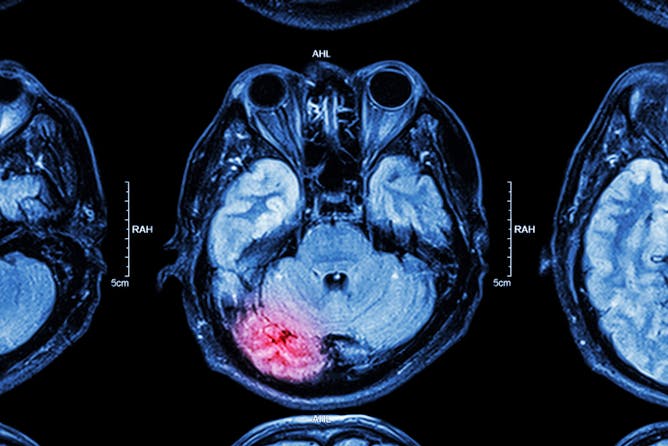

How injuries change our brain and how we can help it recover

Brain injuries damage regions of the brain and this damage can extend post-injury. But other brain regions can pick up the slack, and there are things we can do to help.